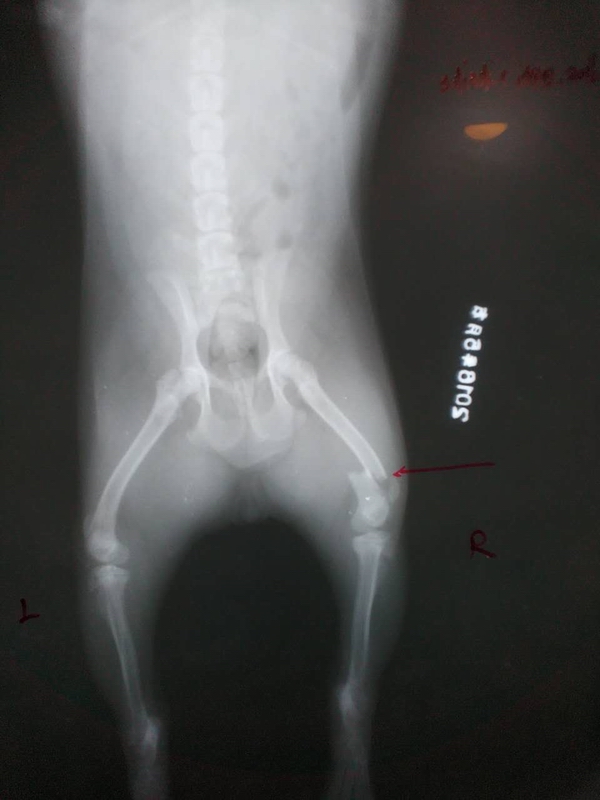

后肢股骨遠端骨折整復手術